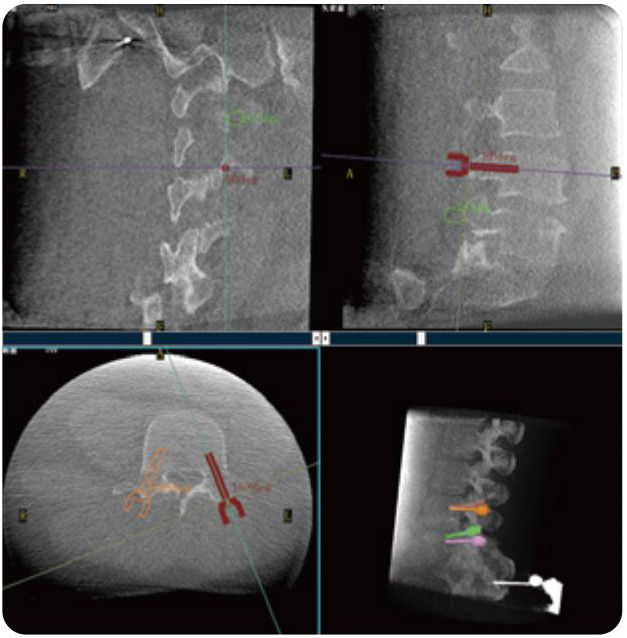

PL300B可應用于多節段脊柱外科手術(shù),輔助醫生定位病灶部位,為脊柱外科手術(shù)(經(jīng)皮椎體成形術(shù)、椎弓根螺釘內固定術(shù)等術(shù)式)提供術(shù)前手術(shù)流程規劃、入釘位置、角度可視化引導,模擬仿真入釘輔助。

PL300B搭配普愛(ài)醫療自主研發(fā)生產(chǎn)的平板3D C形臂,借助一體化自適應配準( 軌跡配準)技術(shù),通過(guò)追蹤C形臂三維采集軌跡,自動(dòng)完成圖像坐標建立和系統坐標配準。配準精度更高,操作步驟少,系統運作效率高。